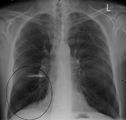

قد يفيد تصوير الصدر بالأشعة السينية والعد الدموي الشامل في استبعاد أسباب أخرى في وقت التشخيص.[52] والسمات المميزة للأشعة السينية هي التمدد الشديد للرئتين، وانبساط الحجاب الحاجز، وزيادة حيز الهواء خلف القص، والأمراض الجلدية، في حين أنها قد تساعد في استبعاد أمراض الرئة الأخرى مثل ذات الرئة ووذمة الرئة أو الاسترواح الصدري.[53] يمكن لصورة الصدر عالية الوضوح باستخدام التصوير المقطعي المحوسب بالأشعة السينية أن تبين توزيع النفاخ الرئوي في جميع أنحاء الرئتين ويمكن أيضاً أن تكون مفيدة في استبعاد أمراض الرئة الأخرى.[11] إذا لم يكن مخططاً لإجراء عملية جراحية، فهذا نادراً ما يؤثر على العلاج.[11] ويتم استخدام غازات الدم الشرياني لتحديد مدى الحاجة إلى الأكسجين؛ ويوصى به لمن يُتوقع أن يكون حجم الزفير القسري لديهم1 أقل من 35%، والذين لديهم تشبع أكسجين محيطي أقل من 92% والذين تظهر لديهم أعراض قصور القلب الاحتقاني.[10] في مناطق العالم التي يشيع فيها نقص مضاد التريبسين ألفا-1، يجب أن يوضع في الاعتبار اختبار الأشخاص المصابين بمرض الانسداد الرئوي المزمن (خاصة من هم دون سن 45 ولديهم نفاخ رئوي يؤثر على الأجزاء السفلية من الرئتين).[10]